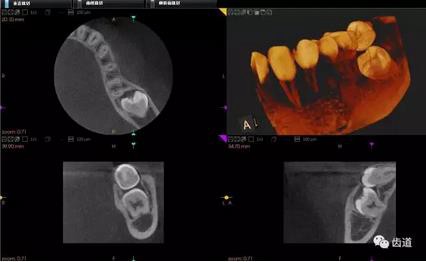

一)牙體牙髓病科

CBCT在牙體牙髓病科治療中,對牙根周圍的解剖關(guān)系、炎癥病變、囊腫等就能夠輕而易舉的進行診斷。甚至與牙齒內(nèi)根管的數(shù)目、走向、分支等都能夠通過牙科CT進行展示,使臨床醫(yī)生的根管治療不再是完全憑手感的“經(jīng)驗科學(xué)”。通過CBCT,還可以對一些“久治不愈“的疑難病例進行檢查和診斷,例如根縱列的診斷、根管內(nèi)異物的定位等,找準(zhǔn)了原因,結(jié)合先進的治療技術(shù)因病施治,使疑難病例的治療變的輕松起來。

1、牙髓根管治療

1)根管治療中牙膠尖充填在CBCT中的影像

2)根管測量